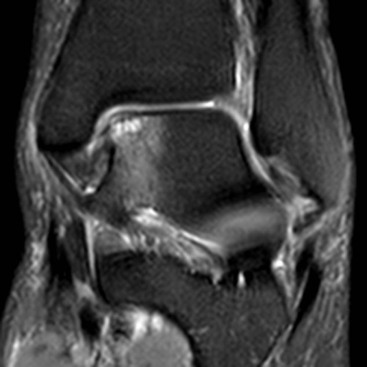

Osteochondral lesion (OCL) of the talar dome is a common cause of persisting deep ankle pain. Most talar OCL occur following trauma, though some medial lesions arise without a history of injury.40 OCL is easily missed on conventional radiographs of the ankle. MRI is very sensitive for OCL, allowing assessment of location and size (Fig. 46-58). The presence of fluid signal around the lesion helps to determine whether the lesion is partially detached, detached or displaced.